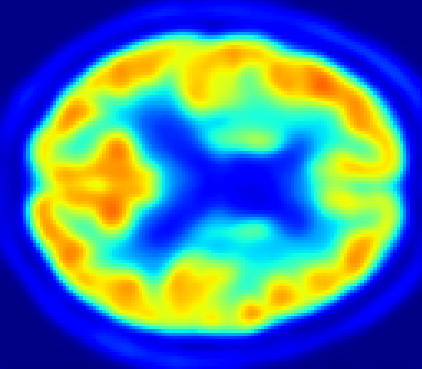

Looking at sample synthetic PET images in Fig. 3, it can be seen that all of the models are able to make reasonable predictions. The outputs of the U-PET and U-PET (no att.) look very similar and are smoothed compared to the input. The pix2pix predicts more details, which seem to be important for the discriminator. However, even though this model has finer predictions, the intensity values are worse compared to the U-PET and U-PET (no att.) as seen in Fig. 2; an example is given in Fig. 3 in the second row.

From a clinical perspective, the synthetic generated PET show a smoother version of the real PET images but keep the same pattern of FDG uptake, especially, hypometabolism in the respective brain areas. This backs up our hypothesis, that MRI contains information that correlates with the functional information of PET images. Moreover, the synthetic PET could be used as complementary visualization for physicians beyond the task of classification.

In Fig. 4, the attention maps of the U-PET are shown for multiple examples. On the one hand, the attention map of the skip connection (AttMap skip) highlights details of the brain structure, which is in agreement with the assumption that the network has to transform the specific structures of the MRI scan into the PET modality. On the other hand, the attention gates used for the classification task rather focus on more specific regions. One can observe a trend that the attention maps used for classification tend to highlight regions which have a low uptake in the PET. Since areas with a lower uptake in the PET correspond to areas with lower functional activity (hypometabolism), this focus area of the network seems reasonable with respect to the classification task.